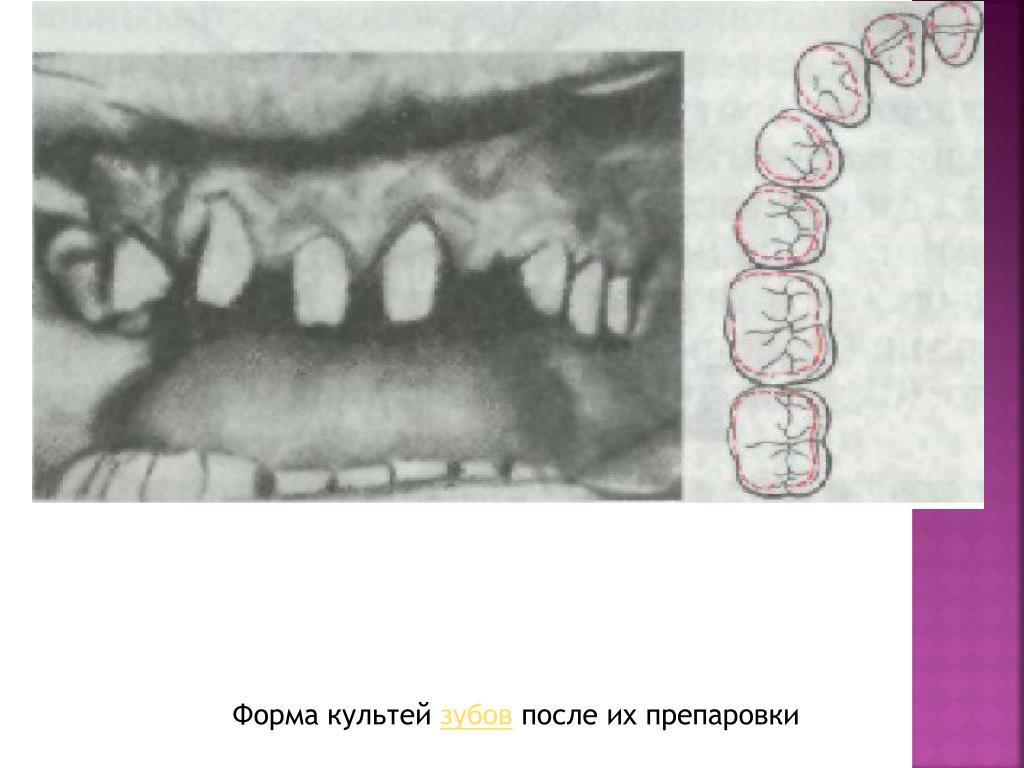

Культя зуба это

Культя зуба это 106 фото